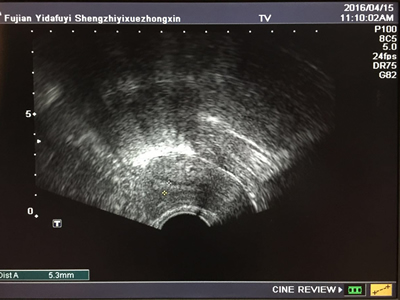

患者临床妊娠B超图像 患者移植后第10天B超内膜图像,内膜5.3mm

此次接诊的患者因年龄偏大,卵巢储备功能不佳,第一次行试管婴儿即无可移植胚胎。为此,中心主任郭玉佳带领的团队为其精心制定了黄体期促排卵方案。经调理2个月后,第二次试管婴儿成功获卵10个。此后,中心实验室主任卢淑庄教授带领团队经过5天的精心培养,获取可移植囊胚5个,但因子宫内膜条件差不允许移植,只得将胚胎冷冻。胚胎冷冻2个月后,郭主任针对患者超薄内膜采用了中心2015年研发的内膜准备新技术调理陈女士的子宫内膜。虽然陈女士的子宫内膜厚度在最终移植时仍然只有5mm,但其内膜形态及其它内分泌指标表明,内膜的着床条件已明显改善。经与患者协商后,同意接受冷冻胚胎解冻移植进行辅助生殖技术助孕。